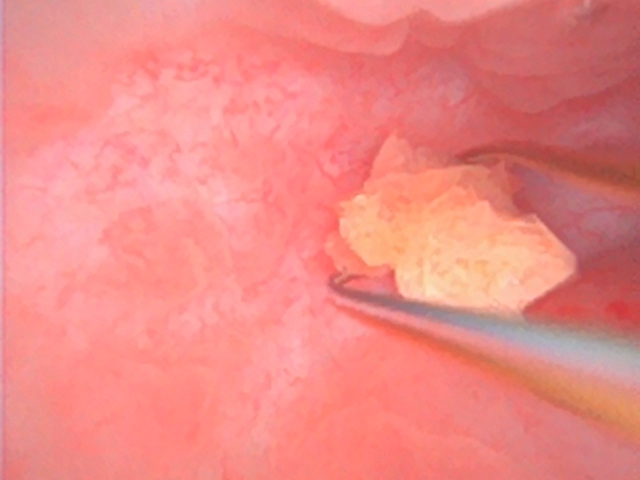

考虑到患者的特殊情况和手术风险,医院迅速组织了多学科会诊,最终决定采用更为先进的微创手术方案:输尿管软镜碎石取石结合X光透视下球囊扩张输尿管膀胱吻合口狭窄。此方案既避免了传统开放手术带来的巨大创伤,又能有效地解决患者移植肾输尿管结石和狭窄的问题。

手术由谷现恩亲自操作,龙建华和泌尿外科副主任医师张军共同协助。整个手术过程中团队紧密协作,精确操作。值得一提的是,手术中采用的X光透视技术虽然能显著提高手术精准度,但对医生而言却意味着额外的辐射暴露。尽管如此,为了患者的安全与康复,张军毫不犹豫地承担了这份风险,充分展现了医护人员救死扶伤、无私奉献的职业精神。